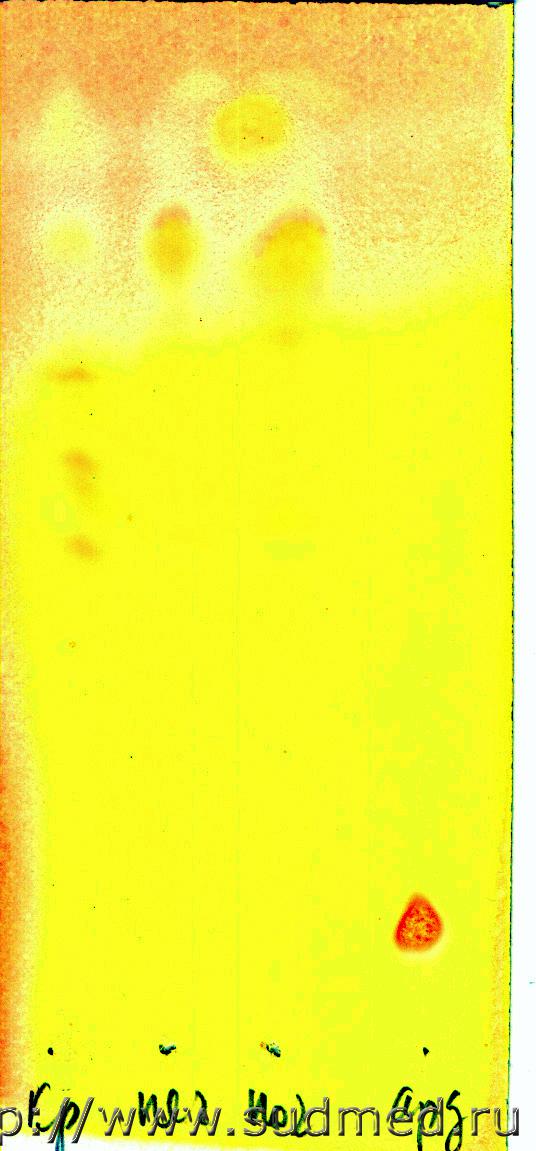

Вот две хроматограммы

Система:

Н-бутанол-пиридин-уксусная кислота лед.-аммиак 25% (9:6:1,8:1,8)

1. ТСХ р-в Драгендорфа по Мунье (насыщение системы 1 час)

2. ТСХ тиоцианат кобальта (насыщение системы 30 мин)

Обратите внимание, чем больше насыщение тем выше Rf. Судебная медицина - Прикрепленное изображениеСудебная медицина - Прикрепленное изображение